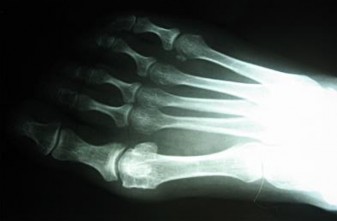

Question 5:

A 55-year-old diabetic patient presents with a swollen, erythematous, and warm foot. Assuming radiographs initially revealed midfoot fragmentation and subluxation, and follow-up radiographs 4 months later demonstrate absorption of fine bone debris and early fusion of large fragments. According to the Eichenholtz classification of Charcot arthropathy, which stage does this represent?

Correct Answer: Stage II (Coalescence)

Explanation:

The Eichenholtz classification describes the natural history of Charcot neuroarthropathy. Stage 0 is the inflammatory phase (erythema, edema, warmth, normal radiographs or mild osteopenia). Stage I (Fragmentation) is characterized by joint subluxation, debris formation, and fragmentation. Stage II (Coalescence) is marked by the absorption of fine debris, early sclerosis, and fusion of larger fragments as the acute inflammation subsides. Stage III (Consolidation/Remodeling) shows remodeling of the bone ends, decreased sclerosis, and a stable (though often deformed) joint.